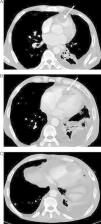

Cervical-thoracic-abdominal computed tomography (CT) was performed for disease characterization and staging, which showed signs of widespread metastasis involving the cervical region, lung, liver and adrenal tissue and bone, as well as confirming the presence of the RV mass (Figure 3A and B). Another mass was detected attached to the pericardium adjacent to the left ventricular lateral wall (Figure 3C).

In the light of these findings, a diagnosis of widespread metastasis from laryngeal cancer was established and palliative treatment was proposed.